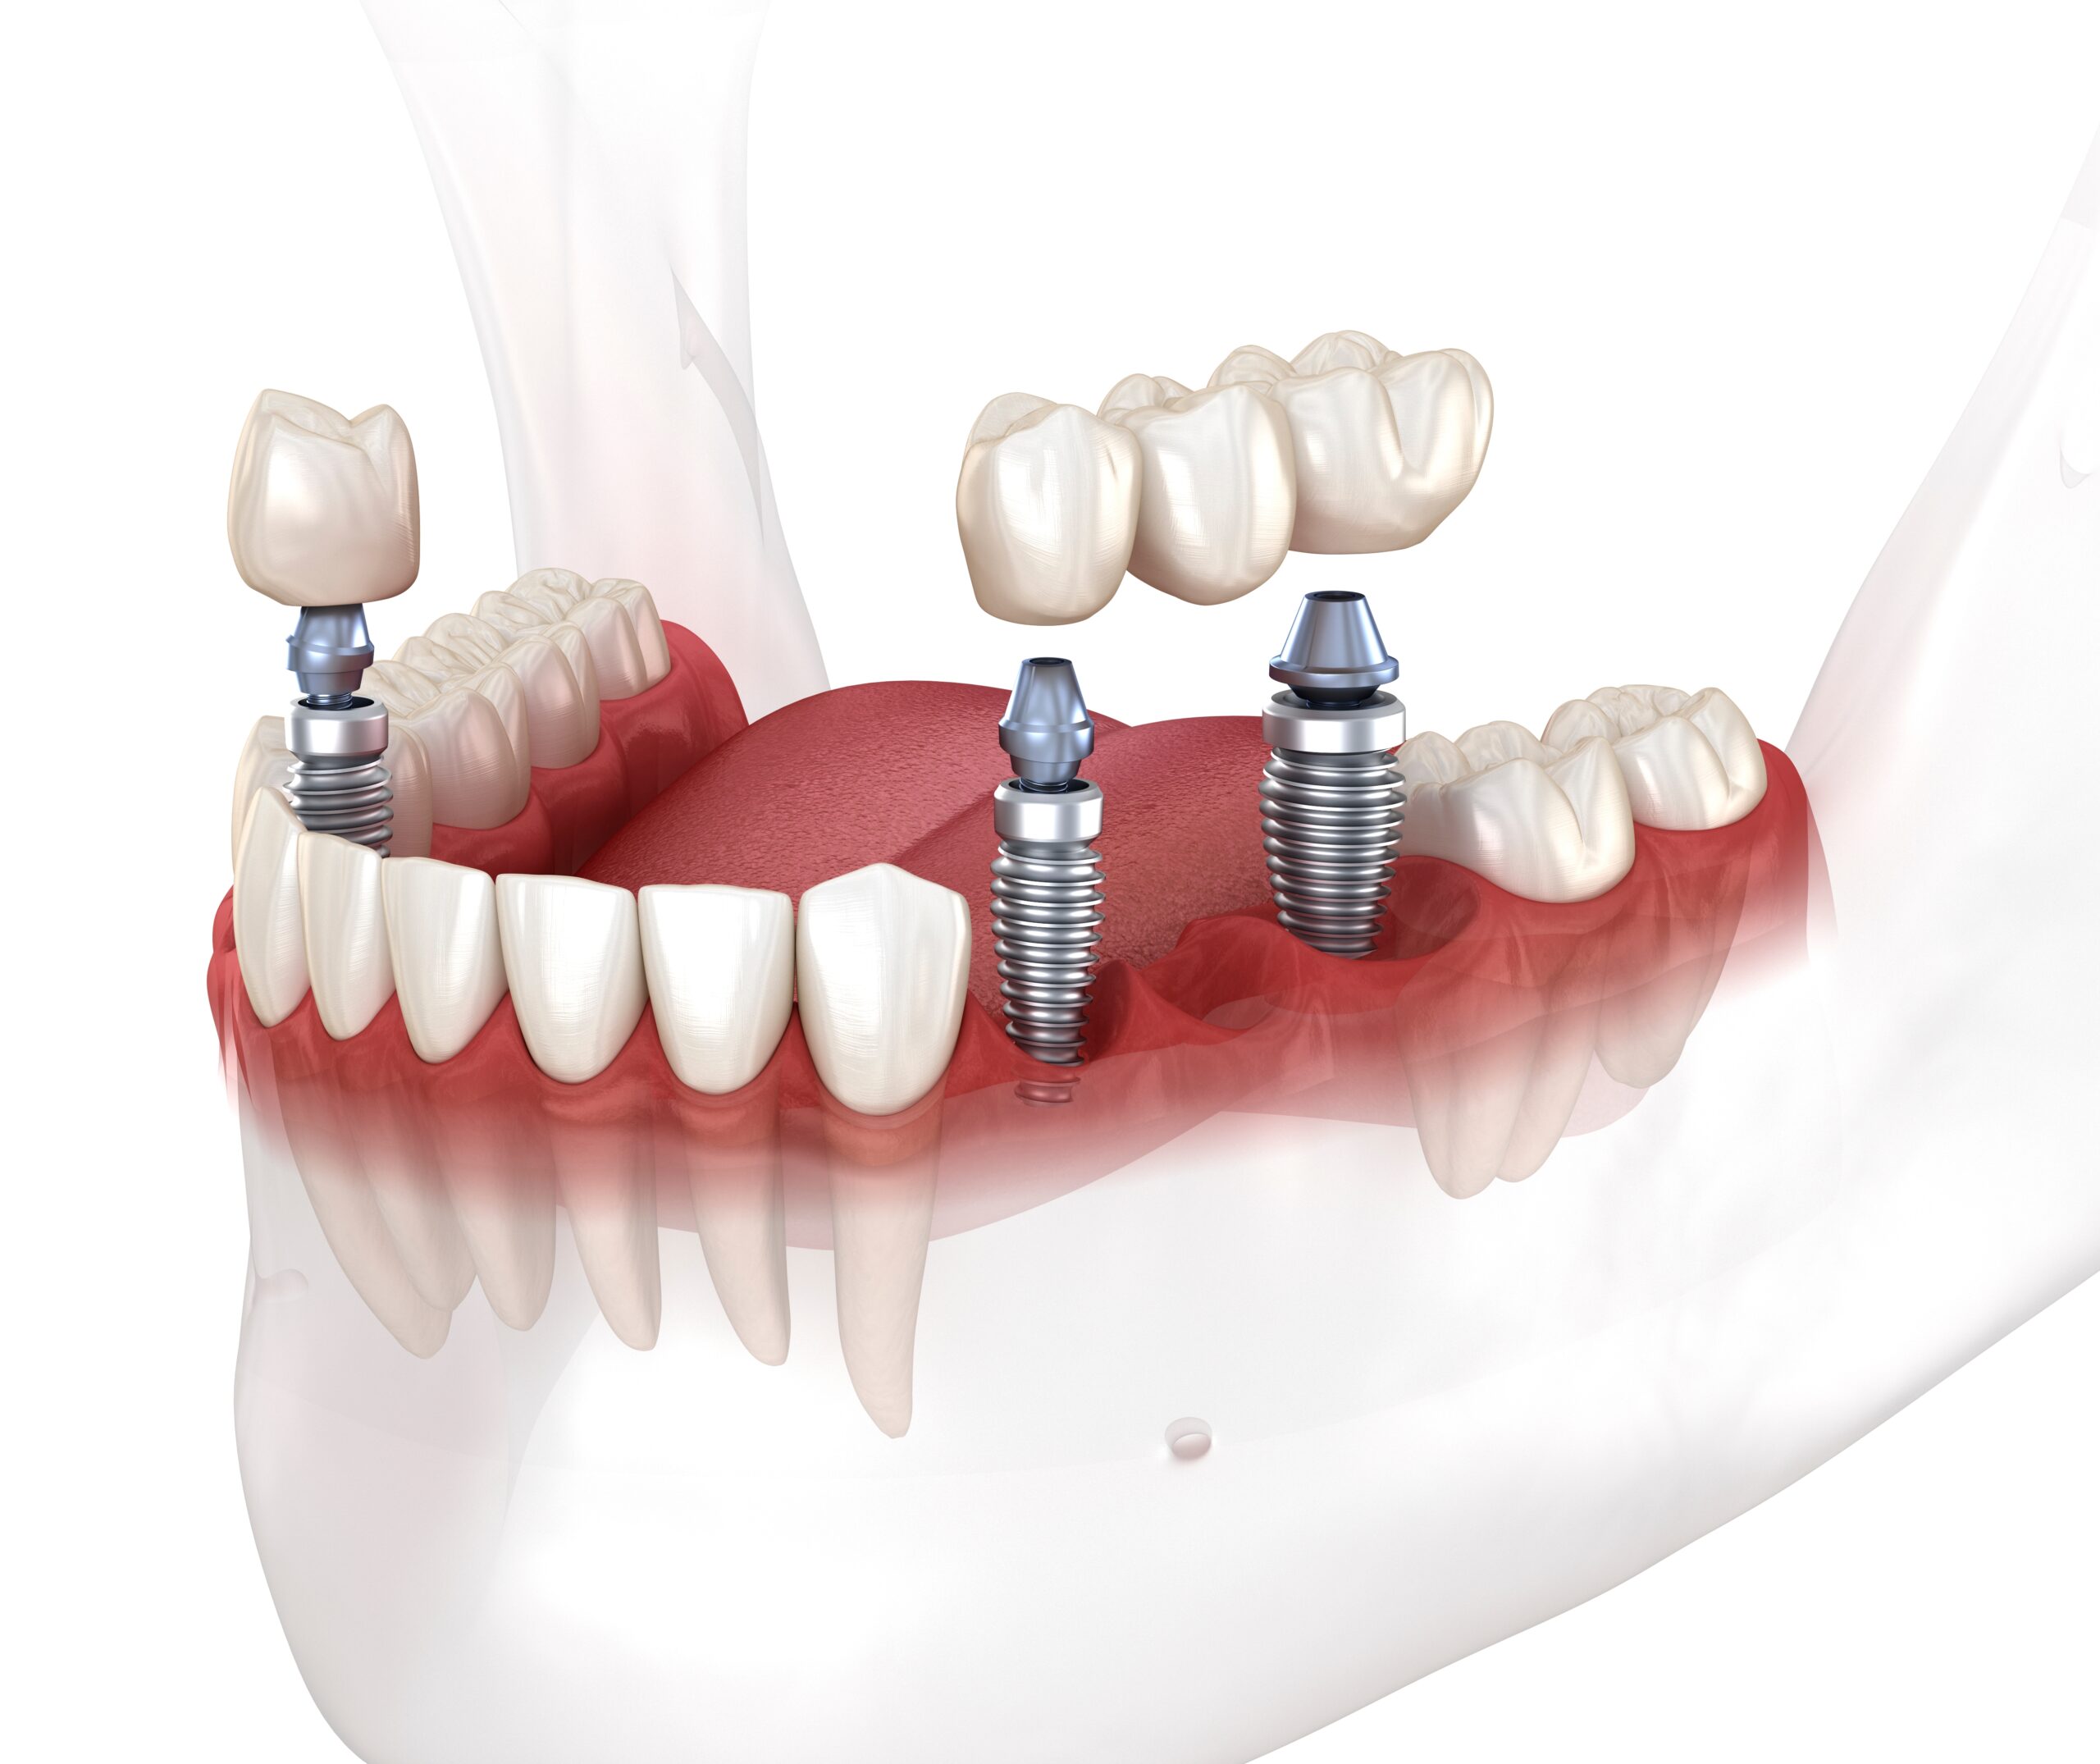

All-on-4® Dental Implants

Transform your smile with a fixed full-arch solution supported by just four dental implants

All-on-6 Dental Implants

A stable and durable option for patients who need additional implant support for long-term function.

Single Dental Implants

A precise and natural-looking replacement for a single missing tooth, designed for long-term stability and esthetics.

Implant Bridges

Replace multiple missing teeth with a fixed implant-supported bridge that restores strength, function, and natural appearance.